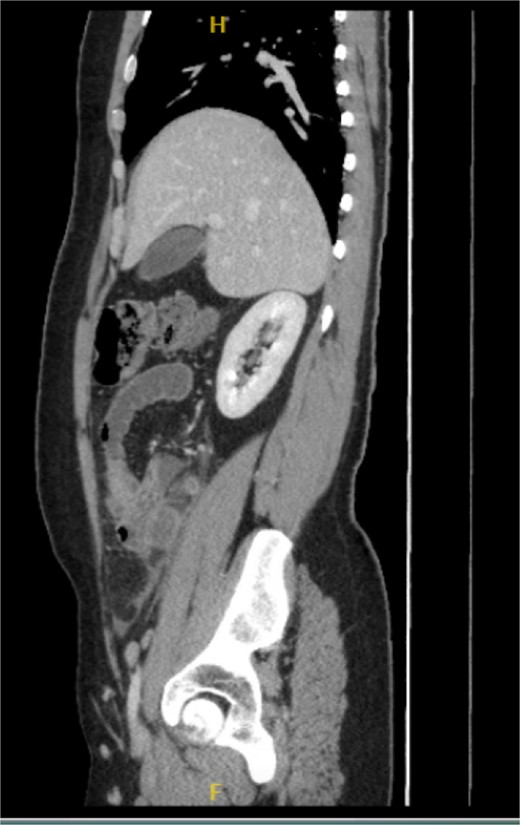

His laboratory tests revealed a white blood cell (WBC) count of 7.8 × 103; all other blood workups were within normal ranges. An abdominal CT scan showed a dilated fluid field in the appendix measuring ~1.8 cm in diameter, with fat stranding, with few areas of decreased well enhancement, and a possible defect in the distal portion of the appendix with phlegm formation (Figs 1–3). All other organs, including the spleen, were unremarkable for any positive findings, with no evidence of free fluid or any splenic injury at the time of the CT scan. The patient was admitted under general surgical care, started on intravenous antibiotics, and was scheduled for laparoscopic exploration and appendectomy. Intraoperative findings included an inflamed appendix and perforation at the midpoint. The patient had an uneventful recovery. The patient was discharged in good condition on postoperative Day 2, with follow-up in the outpatient clinic.

Radiological findings in CT images revealed signs of appendicitis: an enlarged appendicular diameter >6 mm, an appendicular wall thickness >2 mm, mesenteric fat stranding, the presence of an appendicolith, and signs of complications, including perforation or the formation of a peri-appendiceal abscess [10–12]. Careful assessment requires careful medical history taking, physical examination, and radiological investigations with ultrasound or CT scans, which are more sensitive and specific. A high index of suspicion of post-traumatic appendicitis is required because of the rarity of the condition. Treatment includes intravenous antibiotic administration and appendectomy.